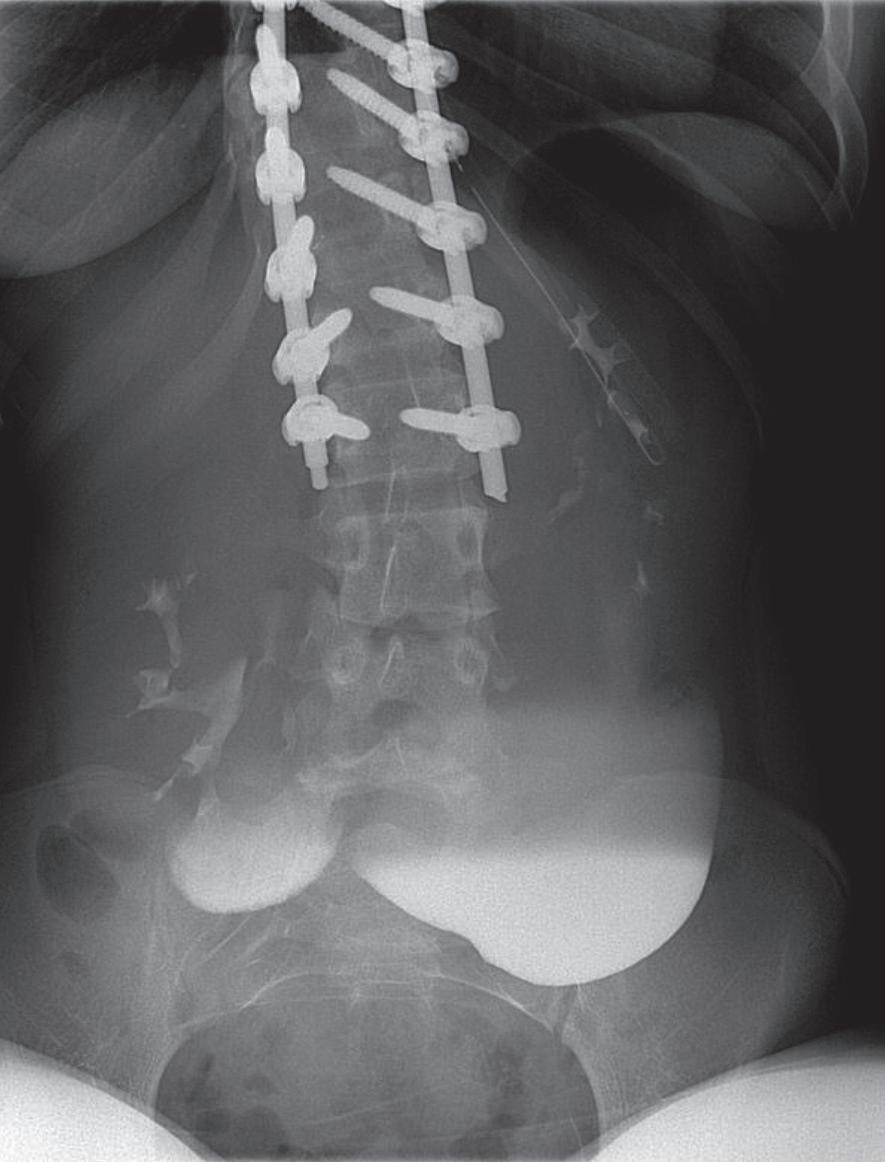

Figura 1. Figura 2.

grafia addome completo, risultata non suggestiva per quadri patologici. Vista la persistenza del dolore, si eseguiva TAC addome con riscontro di ispessimento del muscolo ileopsoas di destra associato a raccolta ipodensa. Visto il sospetto di piomiosite veniva impostata terapia antibiotica ad ampio spettro con ceftriaxone (100mg/kg/die) associata a vancomicina (60mg/kg/die) e si eseguiva RM a completamento del quadro con riscontro di piomiosite a livello dei muscoli ileopsoas, piriforme e otturatore interno e dei tessuti molli contigui, associato a plurime piccole raccolte a grappolo tra i piani muscolari di 6 x 3,5 cm [Figure 1-2]. A circa 48 ore dall’inizio della terapia antibiotica, l’emocoltura è risultata positiva per Streptococcus Pneumoniae multisensibile; veniva quindi sospesa la terapia antibiotica con vancomicina e proseguita con solo ceftriaxone. La terapia antibiotica endovena è stata proseguita per 3 settimane seguita da terapia antibiotica per via orale con amoxicillina per un totale di 7 settimane di terapia. Il follow-up successivo ha mostrato un progressivo miglioramento del quadro infiammatorio con associata riduzione delle raccolte ascessuali.